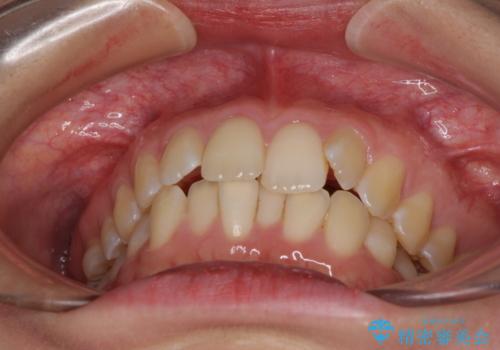

前歯のデコボコを解消 インビザラインによる矯正治療

- 上下前歯のデコボコと深い咬み合わせを気にして来院された患者様です。

インビザラインによる上下歯列の拡大と、IPR(歯と歯の間を削る)にるスペースの獲得により、前歯のデコボコを改善することとしました。

上の前歯をもう少し整えたかったのですが、患者様の治療を早く終了させたいという希望により、細かい叢生を残しての終了となりました。